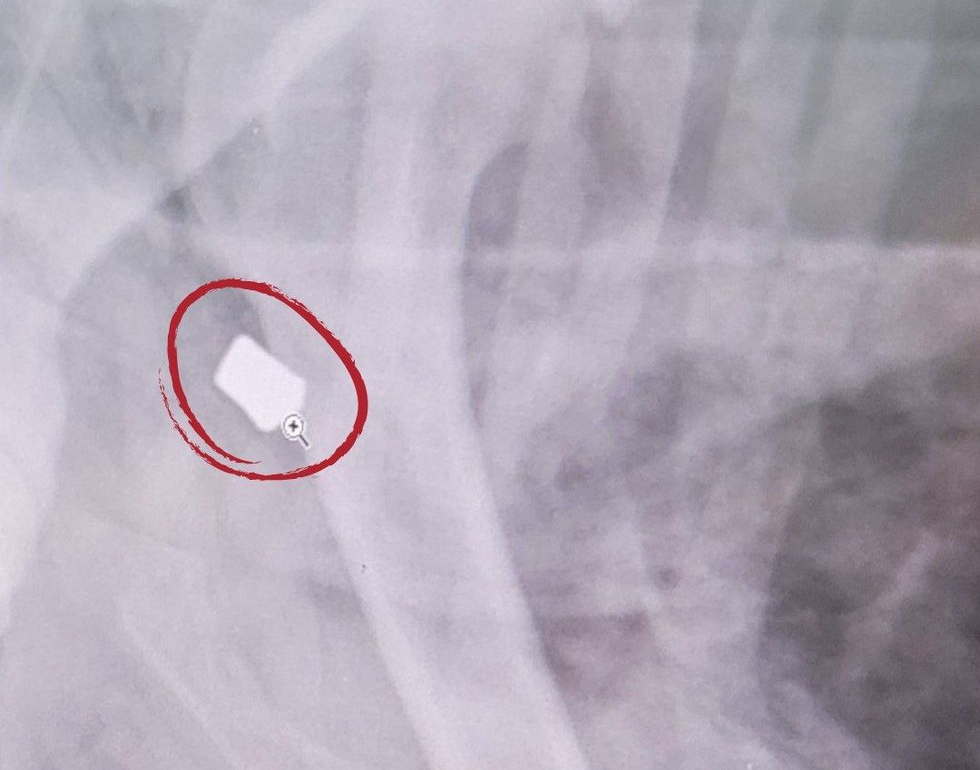

Léandre’s bullet wounds. @spcamontreal | Instagram

X-rays shared by the SPCA present a bullet lodged in Léandre’s physique. Pictures of the bloodied canine unfold throughout social media after his rescue, sparking outrage.